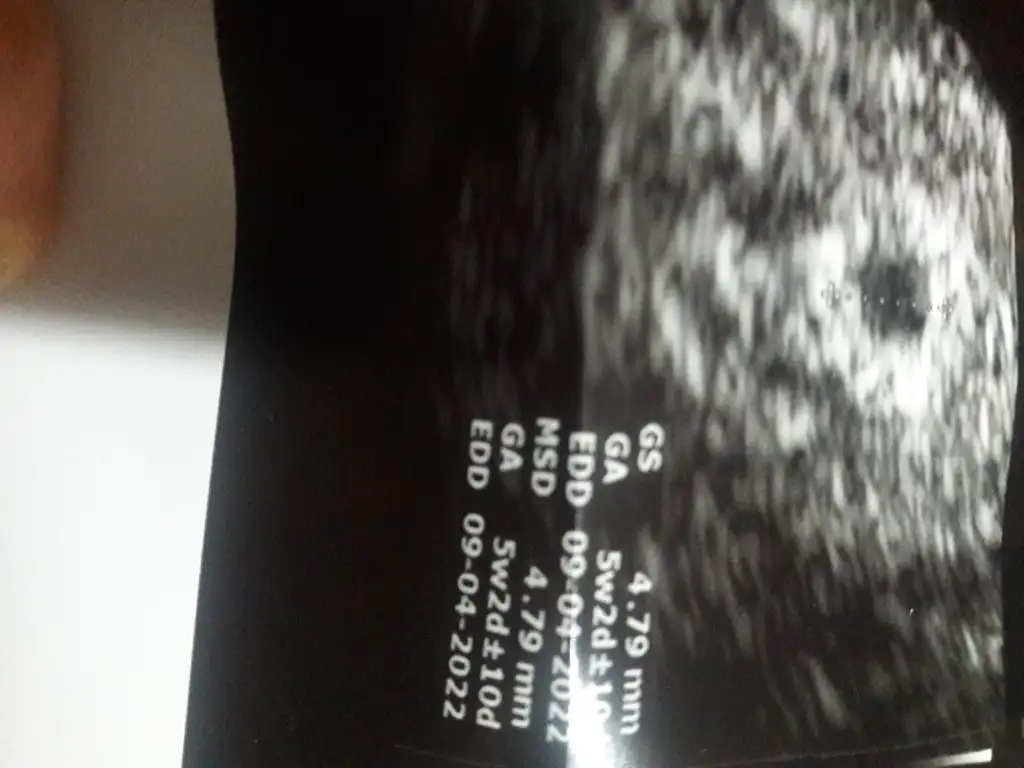

Kızlar selam bugün kontrolüm vardı ama ne doktorum nede ben anlayamadık. Doktorum sende çözemediğim biseyler var kesenin içini hala net göremiyorum gelişen bişey yok ama küçükte olsa fetüs var gibi senin en basta degerlerin düştü sonra yükseldi orda bi 10gün bi kaybımız oldu.o yüzden bu durumda.kestirip atamam küçükte olsa fetüs görünüyo.bu olumluya dönermi bilemem dedi.10gun öncekiyle bugunki ultrason kağıdımı atıyorum bişey söyleyin valla kafam çorba oldu remziye_06 remziye_06

Eklentiler

• 20210809_201234.webp

20210809_201234.webp

22,9 KB · Görüntüleme: 80

• 20210819_115042.webp

20210819_115042.webp

20,6 KB · Görüntüleme: 75